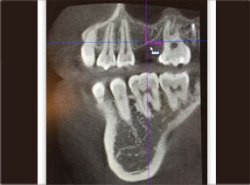

植牙配合鼻竇增高

電腦斷層